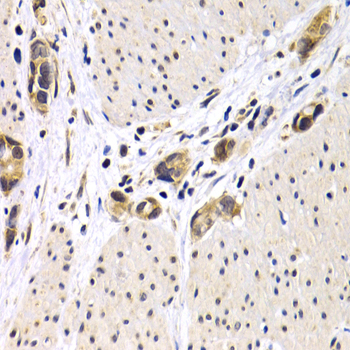

Immunohistochemistry of paraffin-embedded human normal thyroid using ATF2 antibody at dilution of 1:200 (400x lens).

Immunohistochemistry of paraffin-embedded human stomach cancer using ATF2 antibody at dilution of 1:200 (400x lens).